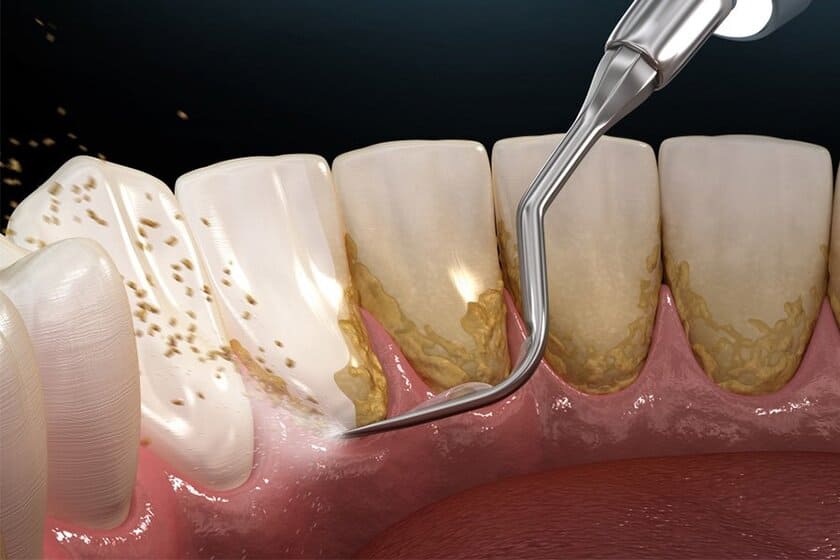

Lấy vôi răng

Điều quan trọng là phải loại bỏ tất cả vôi răng, mảng bám răng gây viêm nướu, tụt nướu. Sau đó, tùy vào tình trạng nướu bị nhiễm trùng mà bác sĩ sẽ chỉ định thêm các loại thuốc đặc trị để nướu hồi phục hoàn toàn.

Lấy vôi răng là phương pháp phổ biến khi xử lý chảy máu chân răng